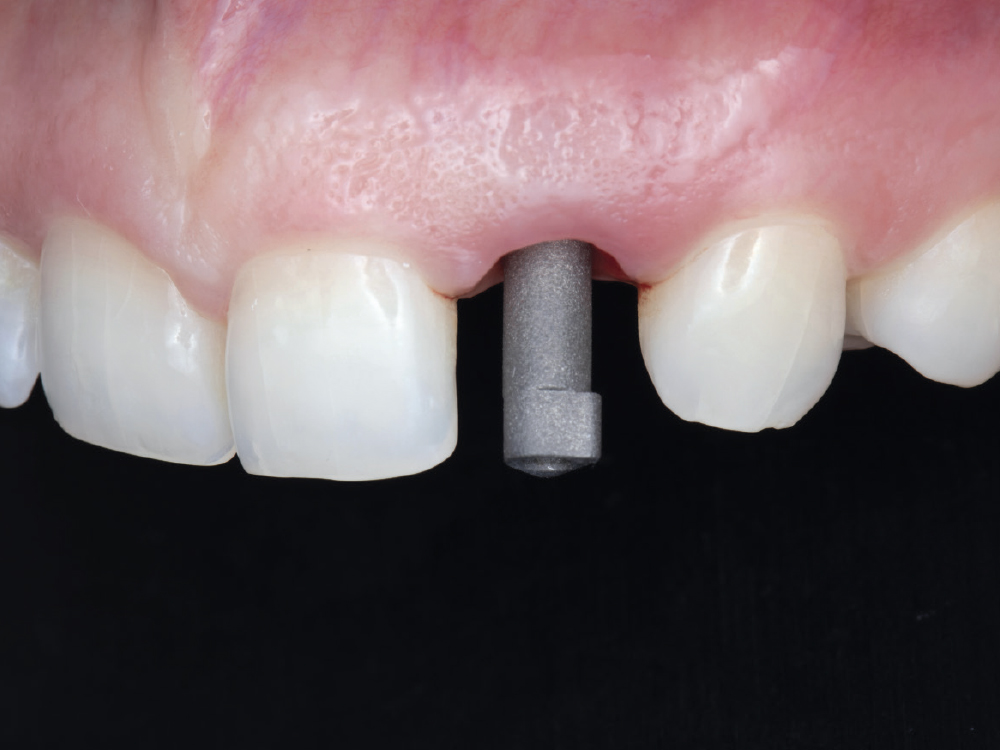

Despite the absence of parafunctional habits and the anterior location, primary stability was not optimal. Therefore, instead of delivering the provisional restoration as initially planned, it was converted into a custom healing abutment. This approach aimed to sculpt and support the soft tissue through the contours of the provisional’s emergence profile.

Figure 12: Despite the absence of parafunctional habits and the anterior location, primary stability was not optimal. Therefore, instead of delivering the provisional restoration as initially planned, it was converted into a custom healing abutment. This approach aimed to sculpt and support the soft tissue through the contours of the provisional’s emergence profile.

The emergence profile created by the custom healing abutment is crucial for maintaining the gingival architecture, ensuring proper alignment of the papilla, margins, and soft tissue. The healing abutment helps retain the patient’s natural tooth appearance as closely as possible throughout the healing process.

Figures 13a, 13b: The emergence profile created by the custom healing abutment is crucial for maintaining the gingival architecture, ensuring proper alignment of the papilla, margins, and soft tissue. The healing abutment helps retain the patient’s natural tooth appearance as closely as possible throughout the healing process.